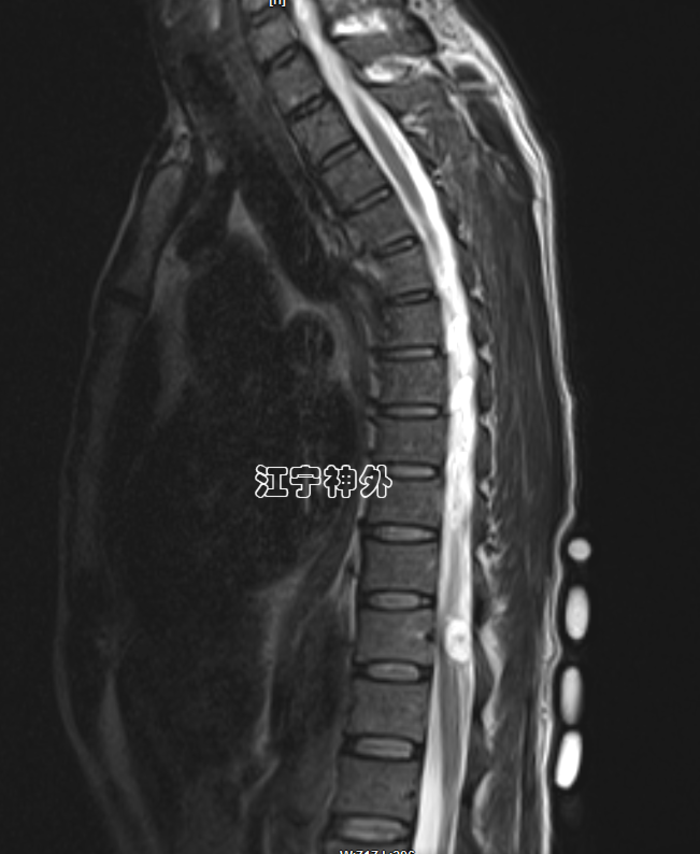

病例2:患者老年男性,因记忆力下降、行走不稳、经常跌倒、有时尿失禁来院,从症状来看,非常符合正常颅压脑积水的表现,而且CT上也确实存在脑室增大,因此就诊神经外科郑学胜主任门诊,并收治入院。然而,术前检查常规做腰穿时,发现脑脊液是草黄色的,压力也很低,提示椎管内存在梗阻性病变。于是,郑主任团队予以全脊柱增强磁共振检查,发现腰1-2水平巨大椎管肿瘤,很显然,上述行走不稳、跌倒、尿失禁等症状是椎管肿瘤引起的。

郑主任阅片发现,从横断面来看,肿瘤几乎占据了椎管全径,正常的脊髓圆锥和神经根已不可辨认,很难说是髓外硬膜下病变还是髓内病变。结合病程很长,脑脊液循环已完全阻断,推测肿瘤与脊髓圆锥、马尾神经根之间,以及肿瘤与硬脊膜之间很可能有明显粘连,所以手术难度较大,手术风险高。

经过充分的术前准备,郑学胜团队于2月16日在术中电生理监测下实施椎管肿瘤切除术;结果手术难度比预估的还要更大,因为不仅肿瘤质地很硬、血供丰富,而且肿瘤位于脊髓圆锥和神经根的腹侧,手术只能在圆锥和神经根的间隙里操作,肿瘤的腹侧又与硬脊膜严重粘连;郑学胜团队经过近6小时的手术,终于将肿瘤完整全切,并且脊髓圆锥和神经根保护良好。

术后磁共振显示,肿瘤无任何残留,脊髓圆锥和神经根恢复正常形态,术后大小便功能、下肢运动恢复正常。术后病理提示:神经鞘瘤伴出血。